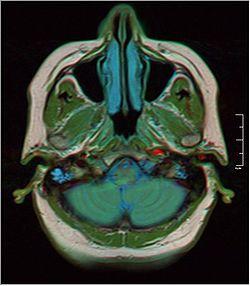

Brain MRI 0106 17.jpg

MRI showing fluid in mastoid air cells